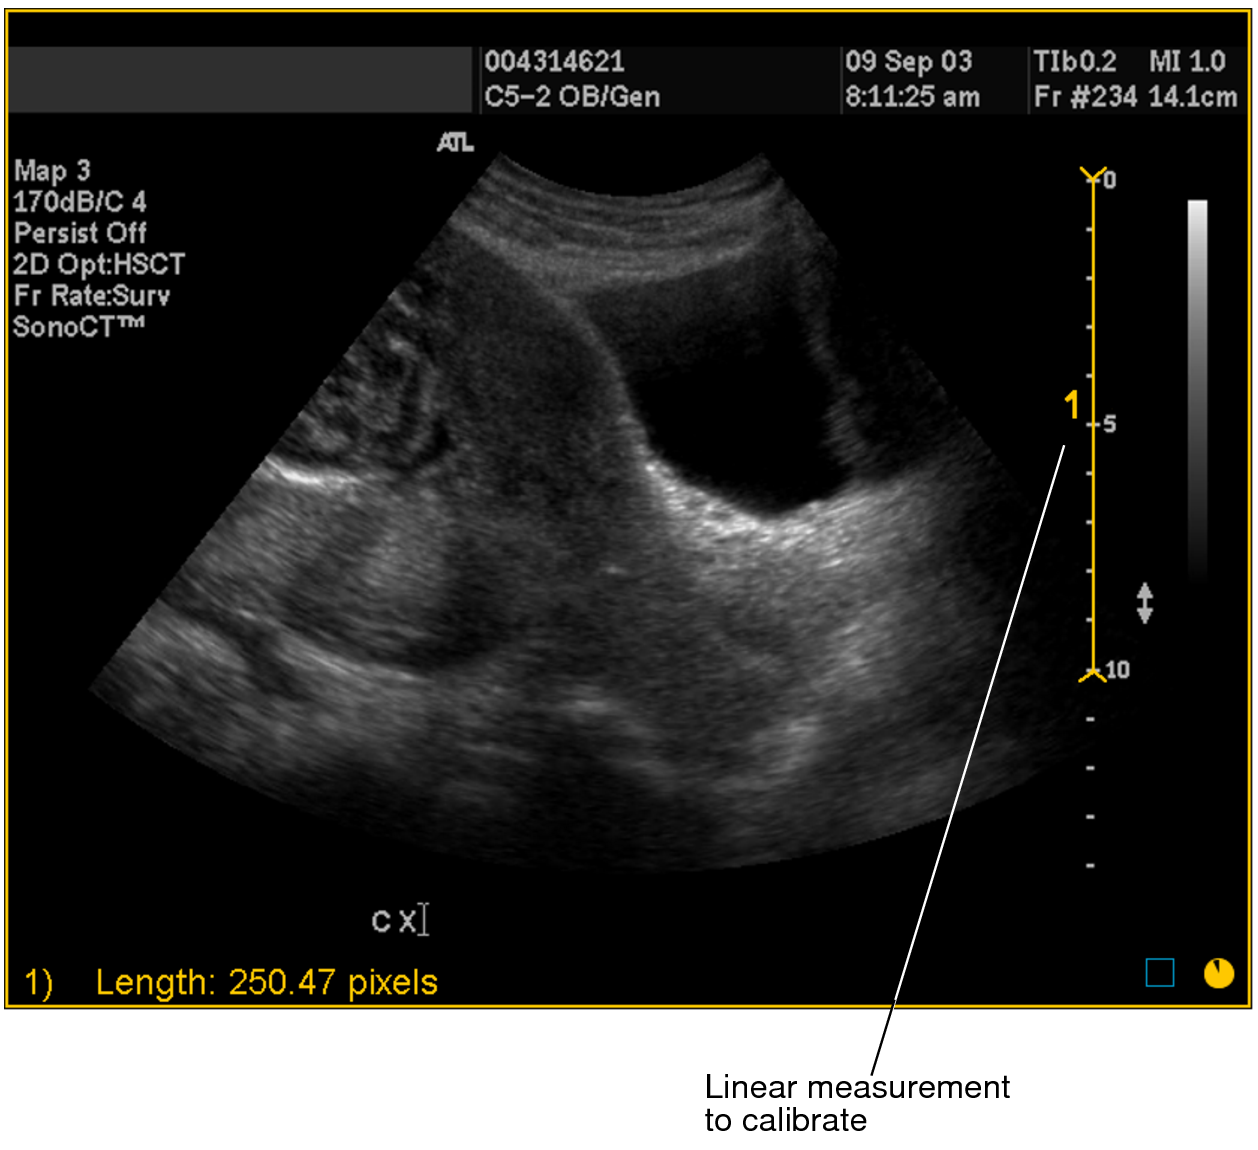

A numbered measurement line appears, and the corresponding length appears in the bottom left corner of the viewport. Notice that the length is displayed in pixels.

Linear measurement to calibrate